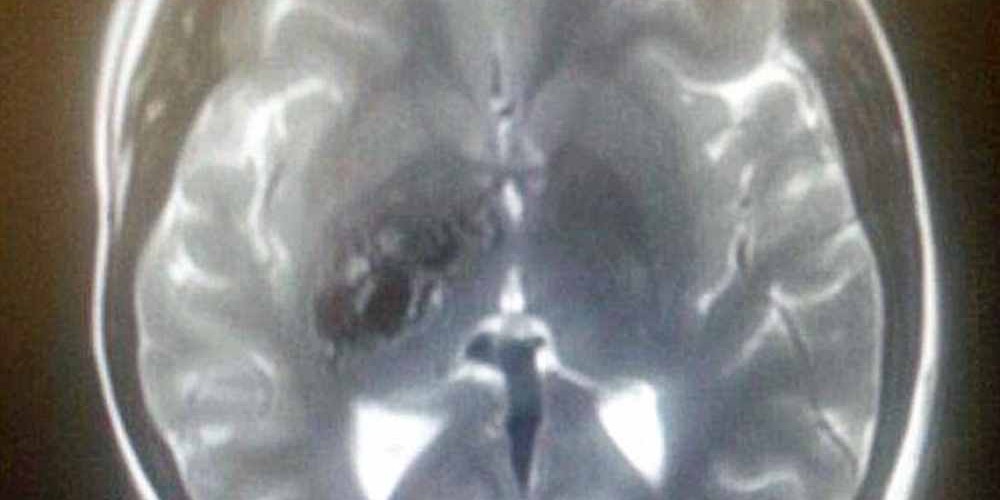

Zoe Roscoe, de 23 anos, de Bolton, foi diagnosticada com MAV cerebral em 2013.

Ela apresentou os sintomas de AVC, e depois de uma varredura, foi informada que a massa em seu cérebro era uma bomba-relógio. Zoe foi rapidamente submetida a uma radiocirurgia, e a massa, removida. A medida deixou seu lado esquerdo fraco e agora ela sofre com a perda de equilíbrio.

“Eu estava na universidade quando, de repente, meu lado esquerdo ficou dormente. Eu fiquei apavorada, pois estava tendo um derrame. Quando cheguei no hospital fizeram uma varredura do meu cérebro, e a MAV foi encontrada”, contou a estudante de psicologia. “Eu nunca tinha ouvido falar disso antes, mas estava apavorada já que os especialistas me explicaram que poderia causar danos cerebrais ou até mesmo a morte caso ele sangrasse”.